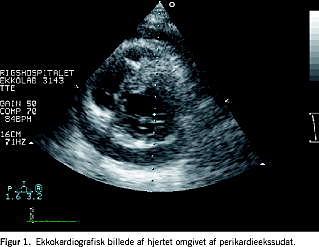

Visualisering af hjertet med ekkokardiografi er uundværlig i vurdering af operationsresultatet og benyttes i stigende omfang til vurderinger af hjertets globale og regionale ventrikelfunktion samt klapforhold (Figur 1). Ultralyd er endvidere essentiel i diagnostik og behandling af perikardie- og pleuraekssudat samt ved anlæggelse af intravasale katetre i de centrale blodkar. Hos både børn og voksne har perioperativ transøso-fageal ekkokardiografi (TEE) været almindelig brugt i mange år [1]. TEE er den eneste anvendelige ultralydsmetode til visualisering af hjerte og store kar under operationen, hvorimod både transtorakal ekkokardiografi (TTE) og TEE anvendes til kardiopulmonal diagnosticering på intensivafdelingen. Forkortede eller simplificerede ekkoprotokoller som f.eks. focus assessed transthoracic echocardiography (FATE) er blevet introduceret på danske hjertecentre [2]. Protokollerne kan læres af de fleste læger, som arbejder med kritisk syge patienter, hvorimod en fuld diagnostisk undersøgelse med f.eks. Dopplermålinger som regel kun udføres af kardiologer. Små bærbare ekkoapparater er nu tilgængelige, hvilket også har bidraget til metodens stigende popularitet.